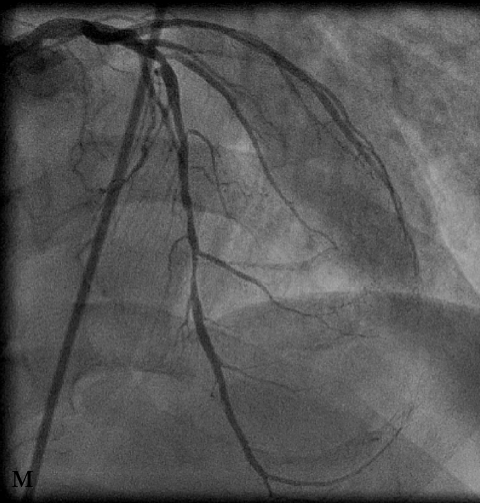

В связи с наличием выраженного пролонгированного стеноза на границе среднего и дистального сегментов ПМЖВ (м) в область сужения был имплантирован стент Cypher с хорошим ангиографическим результатом (н).